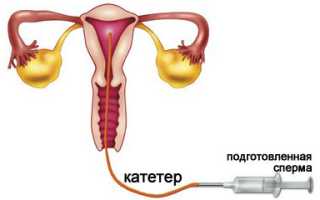

Инсеминация, или искусственная инсеминация – это медицинская процедура, которая проводится при невозможности пары или женщины самостоятельно зачать ребенка. В ходе инсеминации в полость матки при помощи катетера вводят мужскую сперму или обработанные сперматозоиды. Сперму обычно берут либо у супруга или партнера женщины, либо донорскую.

Начинают процедуру с взятия рабочего материала, т.е. мужской спермы примерно за два часа до самой процедуры. Иногда используют замороженную сперму, обычно, при использовании донорского материала. Чаще всего перед процедурой сперму обрабатывают (а иначе процент на успех значительно снижается), и вводят в полость матки.

Проводится инсеминация перед овуляцией, либо естественной, либо вызванной путем стимуляции. Отслеживают овуляцию либо с помощью тестов, либо при помощи УЗИ. За один цикл инсеминацию повторяют трижды. Через две-три недели при благоприятном исходе процедуры тесты на беременность будут положительными.

При инсеминации подготовленные сперматозоиды вводят в маточную трубу, после чего все происходит естественным образом, как и задумано природой: наиболее сильный и быстрый оплодотворяет яйцеклетку, которая затем опускается и закрепляется на стенках матки. При ЭКО в организм женщины переносят уже развивающиеся эмбрионы.